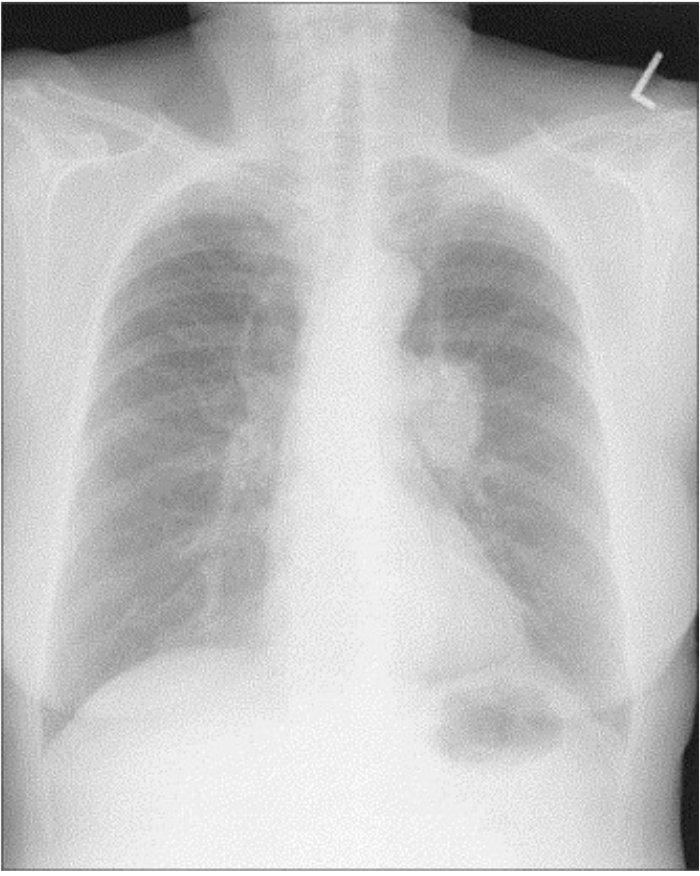

Lung Cancer